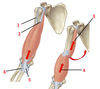

1? 2?

1: Supraspinatus muscle

2: Serratus anterior muscle

1?

1: Trapezius muscle